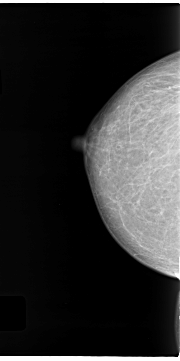

C_0122_1.LEFT_CC

LEFT_CC LINES 4712 PIXELS_PER_LINE 2560 BITS_PER_PIXEL 12 RESOLUTION 50 NON_OVERLAY